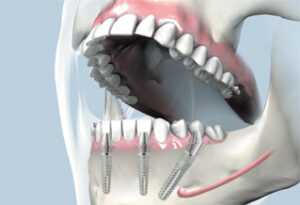

Früher galt die Regel, dass nur mit 6-8 Implantate eine stabile Abstützung für feste Zähne bei Zahnlosigkeit möglich ist. Das All-on-four-Konzept® der Firma NobelBiocare widerlegt diese These: auch mit 4 Zahnimplantaten ist es sicher, einen zahnlosen Kiefer mit festen Zähnen zu versorgen. Die 4 Implantate beim All-on-4-Konzept® nutzen das meist noch günstige Knochenangebot in vorderen Kieferabschnitt. 2 Implantate sitzen im Frontbereich, die beiden anderen Implantate werden weiter hinten schräg platziert, mit der Implantatspitze nach vorne gerichtet. Dadurch wird das Knochenangebot unterhalb der Kieferhöhle im Oberkiefer und über dem Hauptnerv im Unterkiefer voll ausgenutzt. Verletzungen des Nerven oder ein Knochenaufbau unterhalb der Kieferhöhle (Sinuslift) werden so vermieden.

Als weiteren Vorteil bietet das Konzept eine sichere Sofortbelastung durch eine direkte Verblockung der Implantate, sogar mit der Option, einen Zahnersatz am gleichen Tag der Implantat-Operation einzusetzen (feste Zähne an gleichen Tag).

Feste Brücke auf 4 Implantaten: hintere Implantate schräg eingebracht: stabil!

Auch im zahnlosen Unterkiefer ist der Knochenabbau (Atrophie) im Seitenzahnbereich ausgeprägter als in der Frontregion. Hier ist der Grenzpunkt meist der Austrittspunkt des Kinn-Nerven in Höhe des 5. Zahnes. Die hinteren Implantate werden so schräg eingebracht (siehe Bild oben) dass Implantatkopf hinter und die Implantatspitze vor dem Nerven liegt.